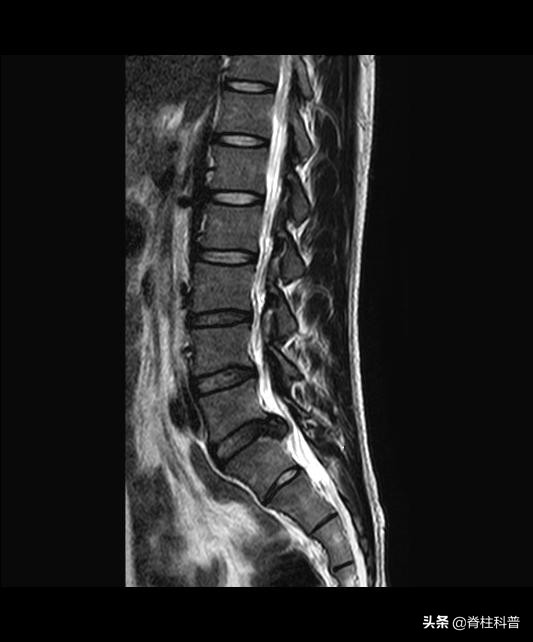

对于腰椎间盘突出症患者,首先要明确该患者是否有手术指征,对于经过 3个月以上系统性保守治疗无效、症状加重影响工作和生活,出现麻木、肌肉萎缩或马尾神经综合征或巨大中央型椎间盘突出患者,应考虑手术治疗。

腰椎间盘摘除术是目前一个较为成熟、有效的外科手段。然而腰椎间盘突出症具有复杂的病因及影像学特点,手术难度大,术后复发导致腰腿疼痛在临床上仍然非常常见,给患者的身心和经济带来极大的负担。

部分患者在术后6个月或者更长时间无症状期或明显缓解期之后,由同一或临近椎间盘间隙再次发作(发作原因不同)导致腰腿疼痛等症状的出现,临床上称之为腰椎间盘突出症术后复发。上一篇科普文有提过,有研究指出,腰椎间盘突出症术后复发率为5%~15%,是术后的常见远期并发症,严重影响手术效果,也是难倒许多脊柱外科医师的问题之一。